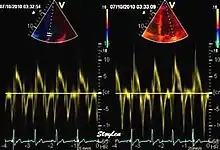

Tissue Doppler echocardiography (TDE) is a medical ultrasound technology, specifically a form of echocardiography that measures the velocity of the heart muscle (myocardium) through the phases of one or more heartbeats by the Doppler effect (frequency shift) of the reflected ultrasound. The technique is the same as for flow Doppler echocardiography measuring flow velocities. Tissue signals, however, have higher amplitude and lower velocities, and the signals are extracted by using different filter and gain settings. The terms tissue Doppler imaging (TDI) and tissue velocity imaging (TVI) are usually synonymous with TDE because echocardiography is the main use of tissue Doppler.

Like Doppler flow, tissue Doppler can be acquired both by spectral analysis (spectral density estimation) as pulsed Doppler[1] and by the autocorrelation technique as colour tissue Doppler[2] (duplex ultrasonography). While pulsed Doppler only acquires the velocity at one point at a time, colour Doppler can acquire simultaneous pixel velocity values across the whole imaging field. Pulsed Doppler on the other hand, is more robust against noise, as peak values are measured on top of the spectrum, and are unaffected of the presence of clutter (stationary reverberation noise).

Colour tissue Doppler

Unlike spectral Doppler, colour tissue Doppler samples velocities from all points of the sector, by shooting two pulses successively, and calculating the velocity from the phase shift between them by autocorrelation. The calculation is slightly different from the true Doppler effect, but the result becomes identical. This results in a single velocity value per sample volume. The result is a velocity field of (nearly) simultaneous velocity vectors towards the probe. The advantage of colour Doppler over spectral Doppler is that all velocities can be sampled simultaneously. The disadvantage is that if there is clutter noise (stationary reverberations), the stationary echoes will be integrated in the velocity calculation, resulting in an under estimate. As pulsed wave Doppler are displayed as a spectrum, the colour Doppler values will correspond to the mean of the spectrum (in the absence of clutter), giving slightly lower values. In the HUNT study, the difference in peak systolic values were about 1.5 cm/s.[26]

The local velocities are not the result of the local function, as segments are moved by the action of neighbouring segments. Thus the velocity differences velocity gradient are the main measure of regional contraction, and has become the most important employment of colour tissue Doppler, in the method of strain rate imaging.[27]